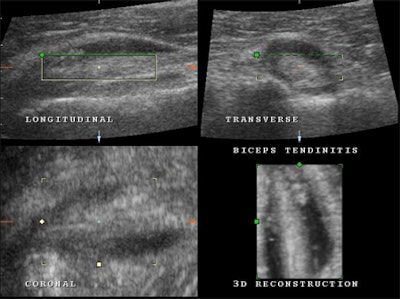

| Multiplanar and 3D representation of biceps tendinitis in a patient suffering from shoulder pain and weakness. Note the focal calcifications at the level of the insertion, enlarged and irregular biceps tendon, and effusion. |